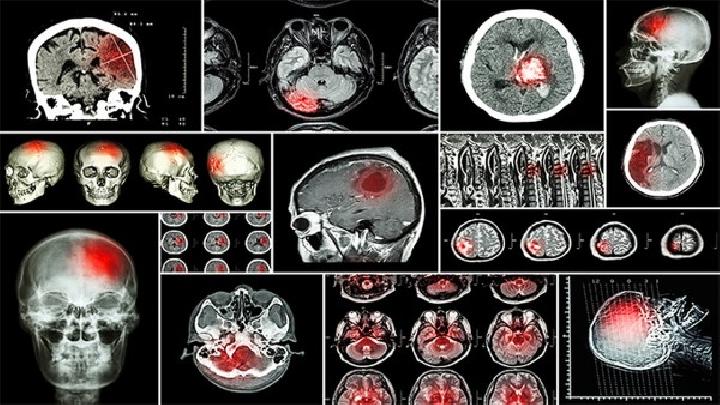

我们都知道脑性瘫痪给我们带来了非常严重的伤害,在生活中出现了脑性瘫痪的时候,我们要帮助患者一起走出疾病的困扰,婴儿先天性脑瘫手术治疗是否可以走出疾病的困扰,患者健康能不能慢慢康复,矫行手术仅能作为一种辅助性的治疗手段,而且在手术前、后均需要不断的进行各种康复治疗。

脑瘫儿童可通过康复训练、药物治疗、手术治疗、辅助器具等方式治疗。脑瘫通常由产前脑发育异常、围产期缺氧缺血、产后脑...

脑瘫病无法完全治愈,但可通过康复训练、药物治疗、手术治疗、辅助器具等方式改善功能。脑瘫是由非进行性脑损伤导致的运...